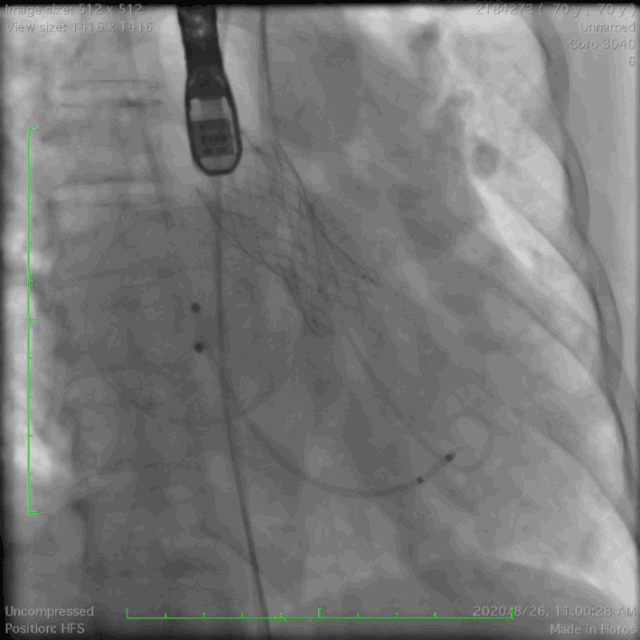

主动脉根部造影

瓣膜定位